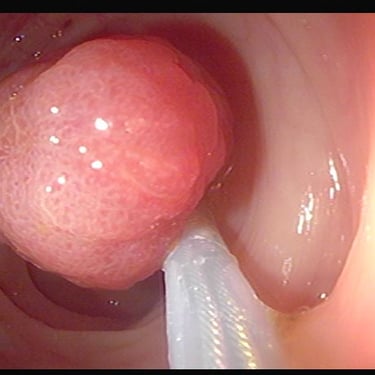

Pólipo de colon

Resección de polipos del colon

(polipectomía)